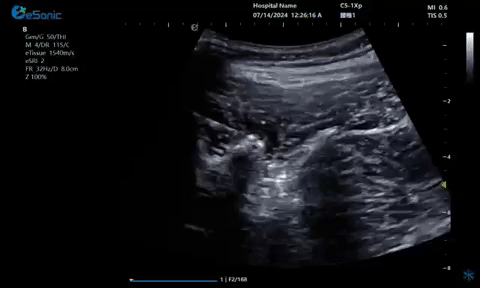

7月12—14日,中国医师协会2024年疼痛科医师年会在山东青岛圆满落幕。大会云集了国内疼痛领域诸多杰出专家学者,大家齐聚一堂,深入研讨疼痛医学领域的最新研究成就与临床实践心得,共同推动学术进步与临床发展。银河官网医疗(ESI)携eHertz系列产品亮相本次大会,凭借国内领先的超声技术和新型“E超”设备成功出圈,展位前吸引了众多访客驻足垂询。该系列产品凭借独特的功能集成,显著提升了设备的精准度和检查效率,为疼痛康复医疗的临床应用提供了全面完善的超声解决方案。值得一提的是,产品应用的穿刺针智能Map技术能够精准和高效的引导医生进行穿刺,既显著提升了医生的工作效率,同时也为患者提供了更优质的医疗服务。

疼痛康复领域中的肌骨超声应用,旨在实现对肌肉、肌腱、韧带、关节、神经、血管、筋膜、滑膜、滑囊、骨膜等组织结构的精确诊断评估。由于超声高频探头对上述机体组织的细微结构具有优异的分辨率,因此能够更为明确地评估这些组织的损伤和炎症状态。同时,超声设备的实时动态评估能力,使得对运动中的相关疾患也能进行准确的评估,这是其他诊断设备所不具备的优势。在康复治疗过程中,肌骨超声还用于介入穿刺治疗,如外周神经阻滞(PNB)、小关节注射、肌筋膜松解术、封闭、小针刀、冲击波治疗等。在超声引导下,这些治疗操作实现了可视化,从而真正意义上实现了精准医疗。以PNB为例,作为一种局部用药方式,其对患者全身干扰小,药物副作用少,且费用较低,因此仍然是临床治疗疼痛的主要方式之一近年来,超声技术在临床康复领域的应用日益凸显其优势。相较于传统的盲穿技术,超声引导下的PNB能够直观显示穿刺和注药过程,无需患者表达异感,避免了反复穿刺给患者带来的痛苦。这种技术显著提高了外周神经阻滞、静脉穿刺的成功率、精确性和安全性,同时减少了不良反应和并发症的发生,为患者带来了福音也相信在不久的将来,eHertz系列产品将会在全球医疗市场上掀起一场技术革新的风暴,让更多的人受益于我国医疗技术的进步。